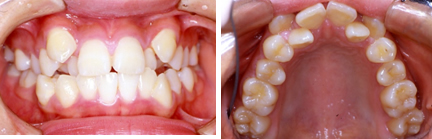

2.混合歯列期(小学2~5年生くらい)の治療

叢生(前歯のデコボコ) 8歳女子

治療前

治療後

※この治療には個人差があります

①主訴:前歯の不揃いを治したい

②診断名あるいは主な症状:前歯部の叢生(アゴと歯の大きさの不調和)

③年齢:8歳

④治療に用いた主な装置:ライトワイヤー法

⑤抜歯部位:非抜歯

⑥治療期間:約1年半

⑦治療費:検査:38,500円

基本矯正費用:440,000円~

調整料:6,600円 (ひと月に1回)

⑧リスクと副作用:治療開始後数日は噛むときに痛みがあります。

虫歯予防のため適切な歯磨きが必要

装置が破損することがあるため、その時は連絡をすること

後戻り防止のため、保定装置の装着が必要である。

第2期(永久歯列期)での仕上げの治療が必要になる場合もある